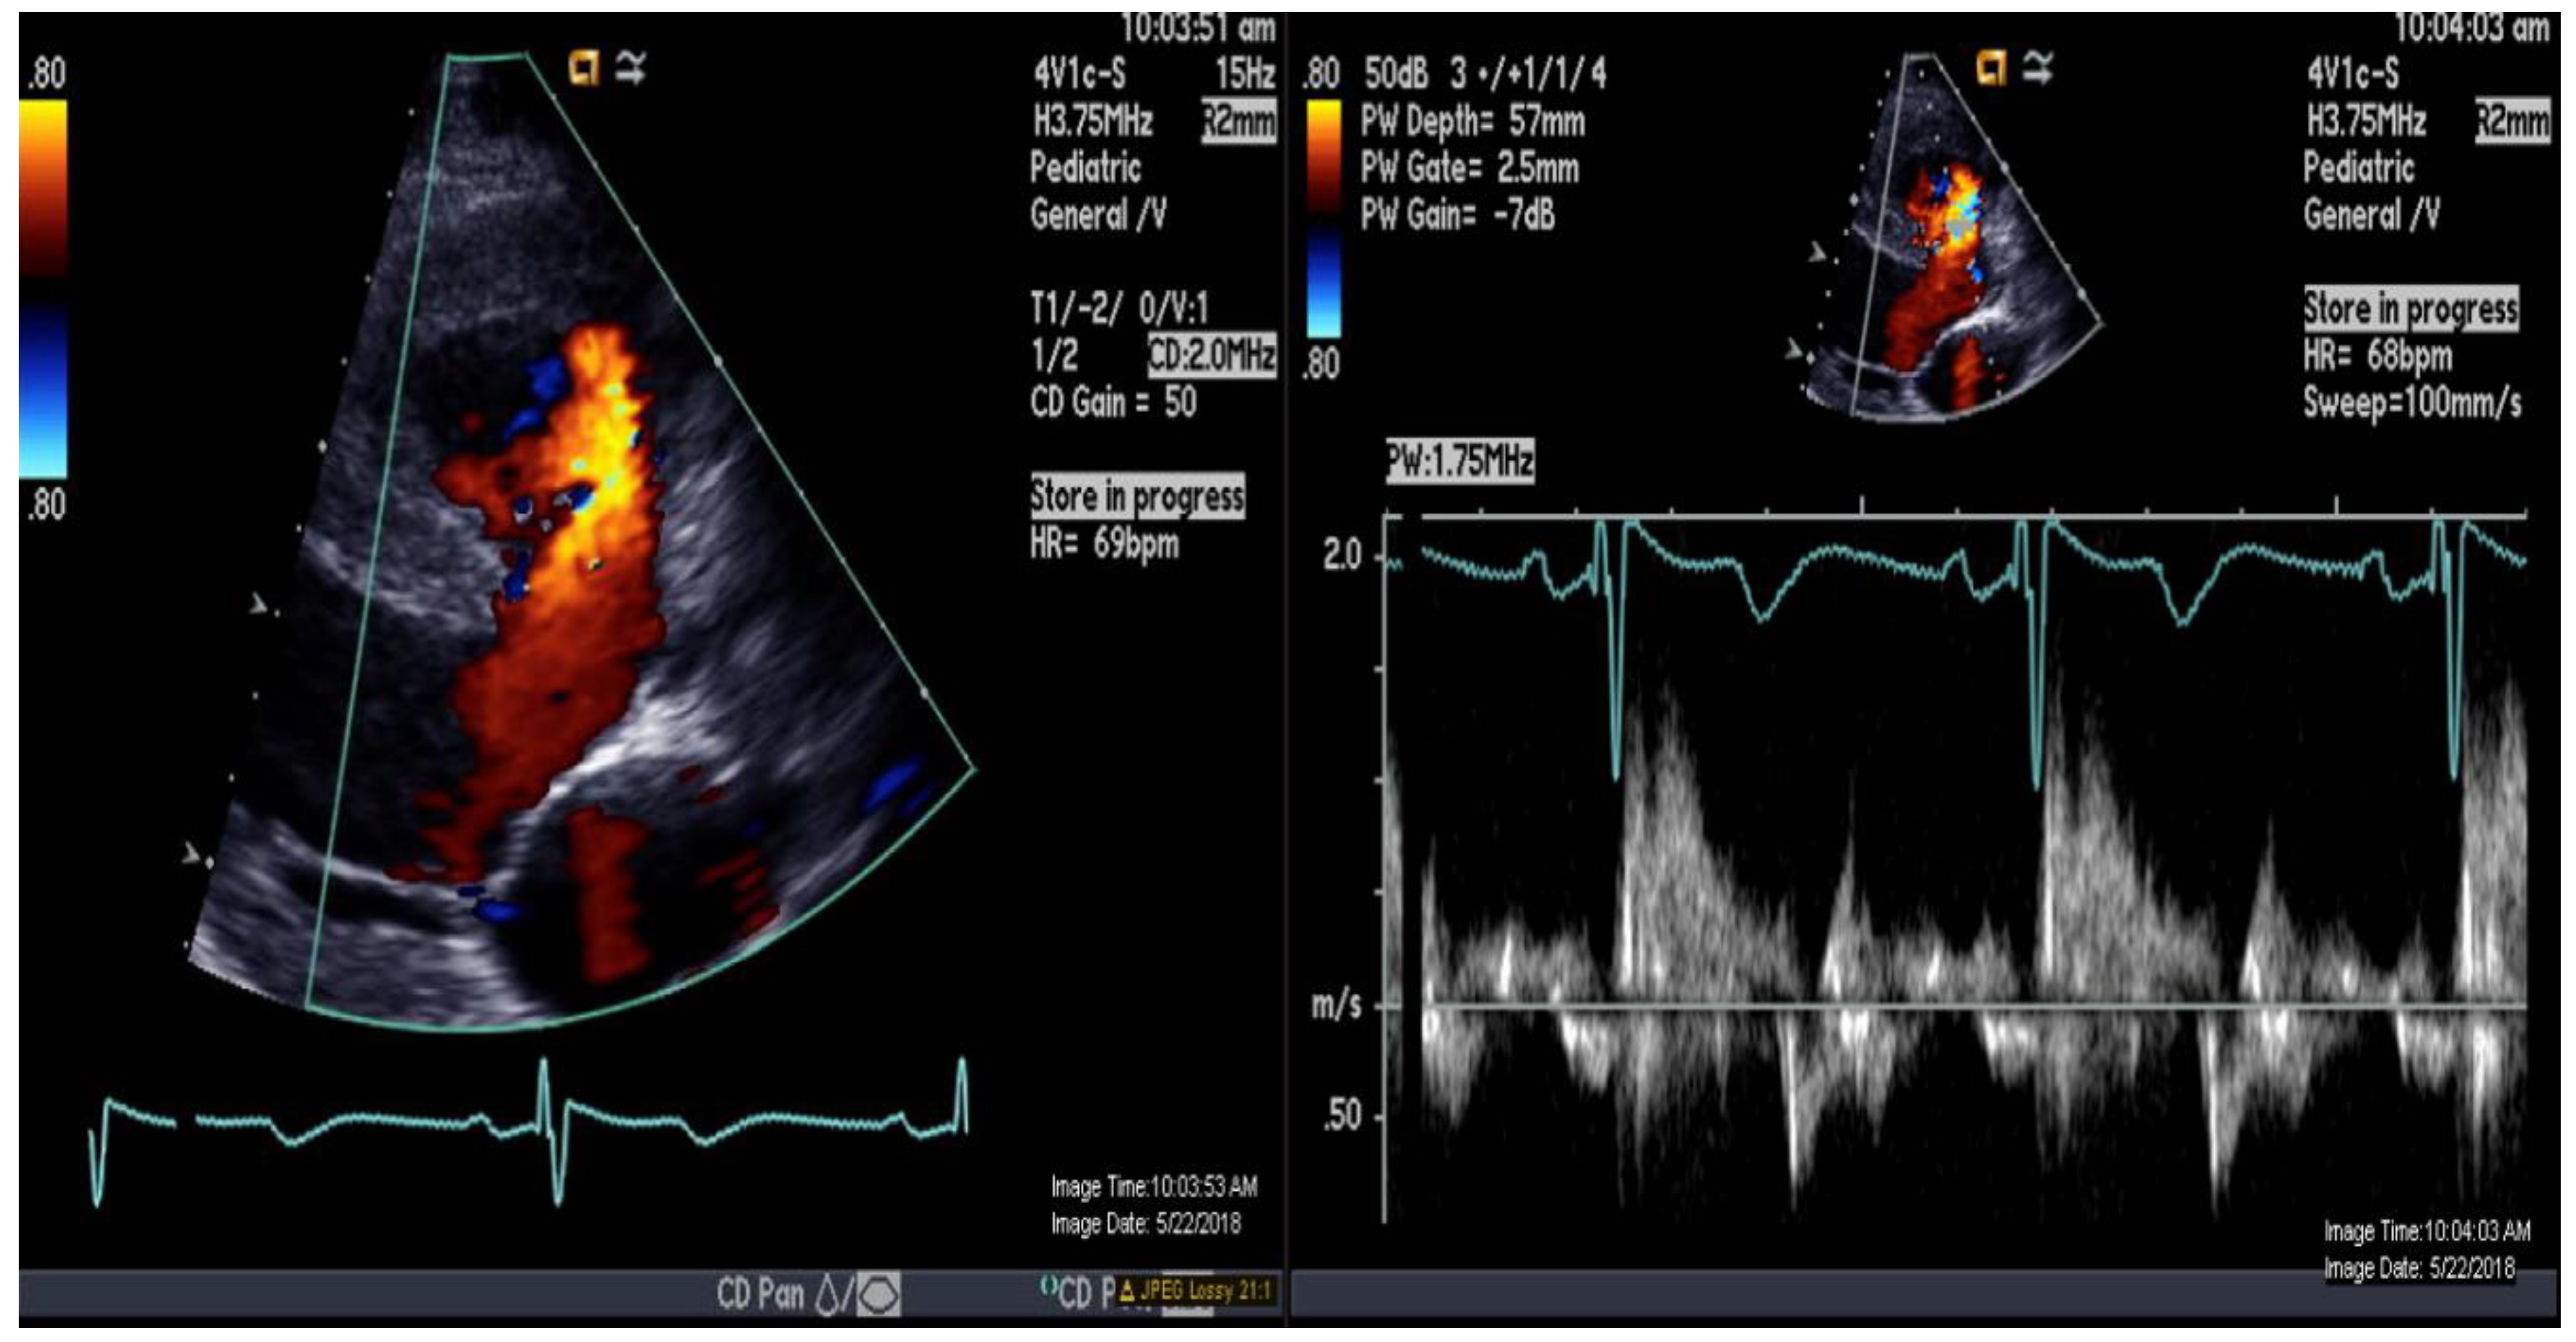

A 16-year-old adolescent boy, trisomy 21 with multiple cardiac shunts (VSD, and PDA) and echocardiography-estimated RV systolic pressure 73 mm Hg plus right atrial pressure based on tricuspid regurgitation jet (Figure 1). He was considered inoperable due to bidirectional shunting across VSD (Figure 2) by echocardiography and referred to our institution for evaluation. He underwent CMR-guided RHC and pulmonary vasodilator testing in the Phillips Ingenia 1.5 Tesla MR/catheter hybrid laboratory suit (Figure 3). The hybrid Cath-CMR setting and iCMR procedural details at Children’s Medical Center, University of Texas Southwestern Medical Center, was described previously [4].

Figure 2.

Color-and-pulse Doppler showing bidirectional shunting across a large perimembranous ventricular septal defect.